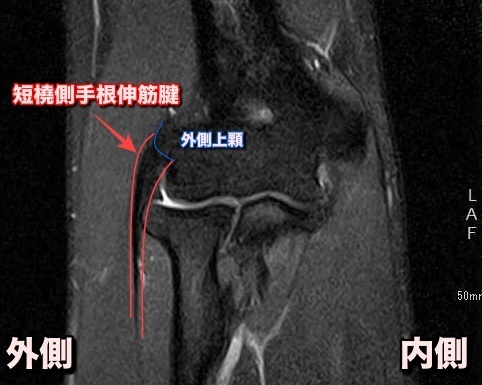

MRI検査

Magnetic Resonance Imaging(磁気共鳴画像法)の略称で、強力な磁力を使用して、身体の断面図を撮影する方法です。

MRIはレントゲン・CTとは違い、放射線などを使用しないため、被ばくの心配はありません。

時間や費用などが掛かりますが、肘関節の周辺を含めた全体像の把握や腱の損傷範囲や程度・関節内の異常まで精査することが可能です。